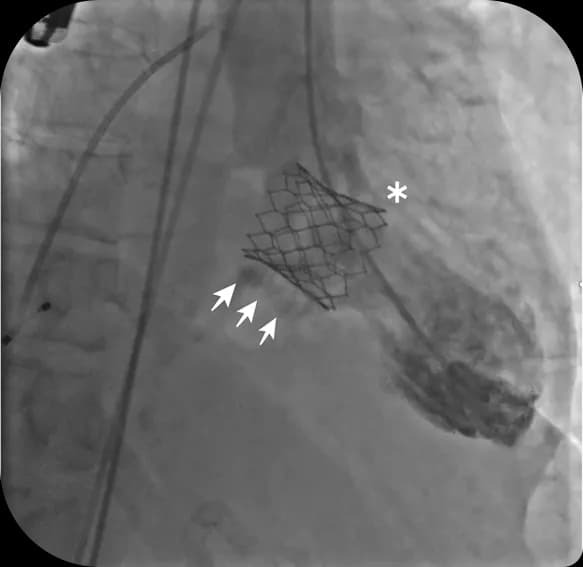

TMVR procedure performed via catheter approach through the femoral vein, often under conscious sedation

When this happens, Valve-in-Valve TMVR offers a minimally invasive alternative to repeat open-heart surgery. Instead of replacing the old valve entirely, a new transcatheter valve is placed inside the existing one.

Real-time 3D echocardiography and cardiac CT help in accurate valve sizing and positioning.